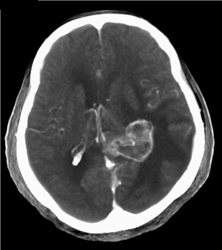

Orbital Fracture With Bleed Into Sinus